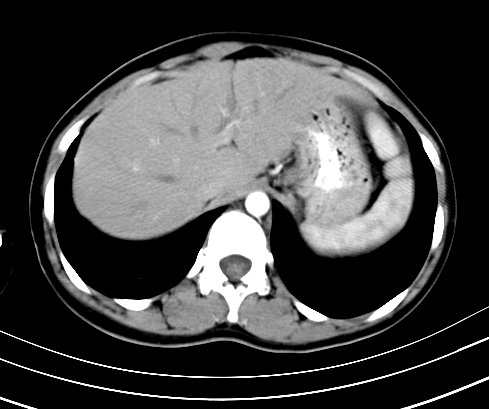

腹部平扫